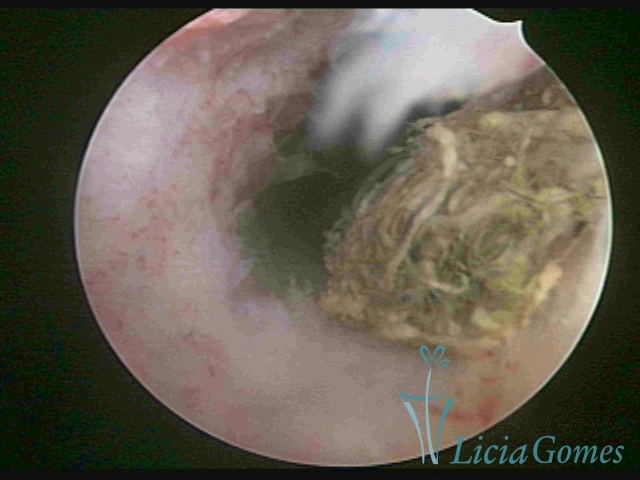

Cavidade uterina com DIU, envelhecido e dobrado